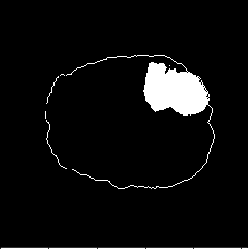

There are 210 HGG cases in the training data. Because we have no access to the test data of the BraTS2018 Challenge, we split the 210 cases into train (170 cases) and test (40 cases) sets. The train set is then sorted according to the tumor size and divided into 10 subsets equally, which are treated as data in 10 distributed medical entities. There are 11,057 images in the train set and 2,616 images in the test set. We conduct the following segmentation experiments: (1) Real-All. Training using real images from the whole train set (170 cases). (2) Real-Subset-n. Training using real images from the -th subset (medical entity), where . There are 10 different experiments in this category. (3) Syn-All. Training using synthetic images generated from a regular GAN. The GAN is trained directly using all real images from the 170 cases. (4) AsynDGAN. Training using synthetic images from our proposed AsynDGAN. The AsynDGAN is trained using images from the 10 subsets (medical entities) in a distributed fashion.

In all experiments, the test set remains the same for fair comparison. It should be noted that in the Syn-All and AsynDGAN experiments, the number of synthetic images are the same as that of real images in Real-All. The regular GAN has the same generator and discriminator structures as AsynDGAN, as well as the hyper-parameters. The only difference is that AsynDGAN has 10 different discriminators, and each of them is located in a medical entity and only has access to the real images in one subset.

(a) Image

(b) Label

(c) Real-All

(d) Syn-All

(e) Real-Subset-6

(f) AsynDGAN

(a) Input

(b) AsynDGAN

(c) Real

4.4.2 Results

The quantitative brain tumor segmentation results are shown in Table 2. The model trained using all real images (Real-All) is the ideal case that we can access all data. It is our baseline and achieves the best performance. Compared with the ideal baseline, the performance of models trained using data in each medical entity (Real-Subset-110) degrades a lot, because the information in each subset is limited and the number of training images is much smaller.

Our AsynDGAN can learn from the information of all data during training, although the generator doesn’t “see” the real images. And we can generate as many synthetic images as we want to train the segmentation model. Therefore, the model (AsynDGAN) outperforms all models using single subset. For reference, we also report the results using synthetic images from regular GAN (Syn-All), which is trained directly using all real images. The AsynDGAN has the same performance as the regular GAN, but has no privacy issue because it doesn’t collect real image data from medical entities. The examples of synthetic images from AysnDGAN are shown in Figure 5. Several qualitative segmentation results of each method are shown in Figure 4.